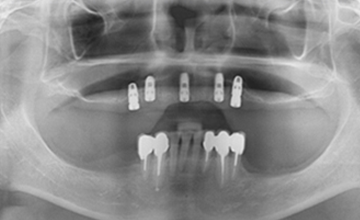

2개에서 4개 정도의 임플란트를 심고,

그 위에 딱 맞게 고정되는 틀니를 끼우는 방식입니다.

틀니 안쪽에 작은 고정장치가 있어

단추처럼 임플란트에 ‘딸깍’하고 끼워지는 구조라

일반 틀니보다 훨씬 덜 흔들리고 안정감이 좋습니다.